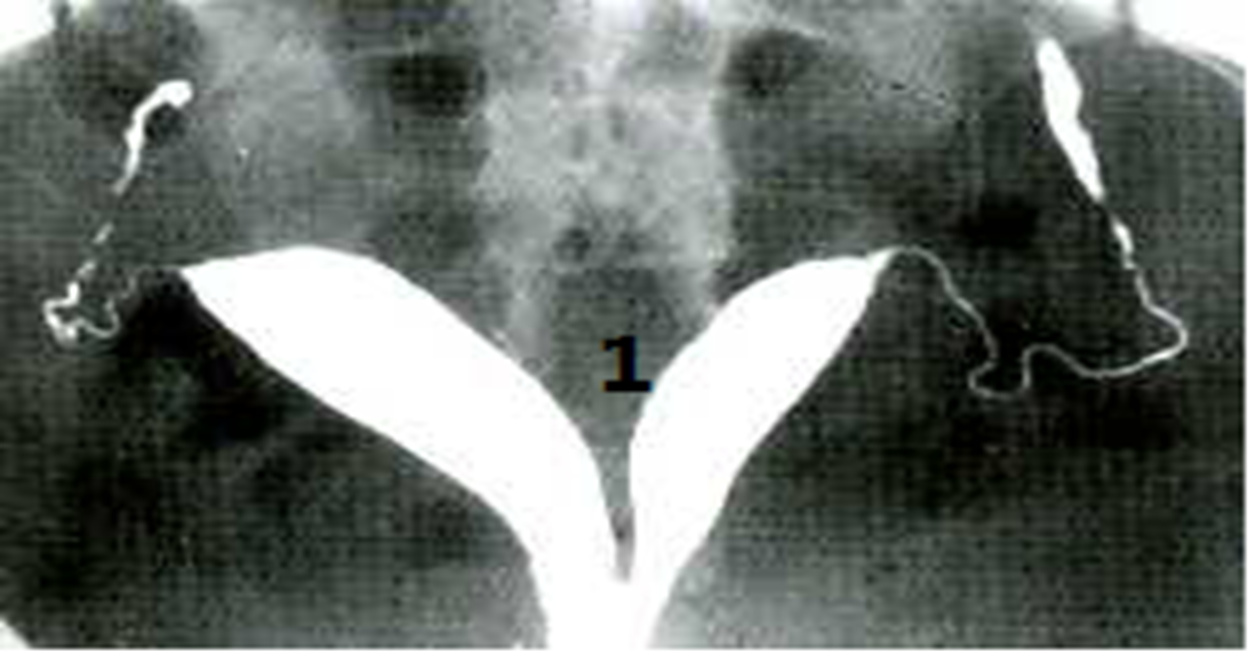

Hysterosalpingogram

A divided uterus can be seen. An angle of less than 75° between the uterine horns is suggestive of a septate uterus.